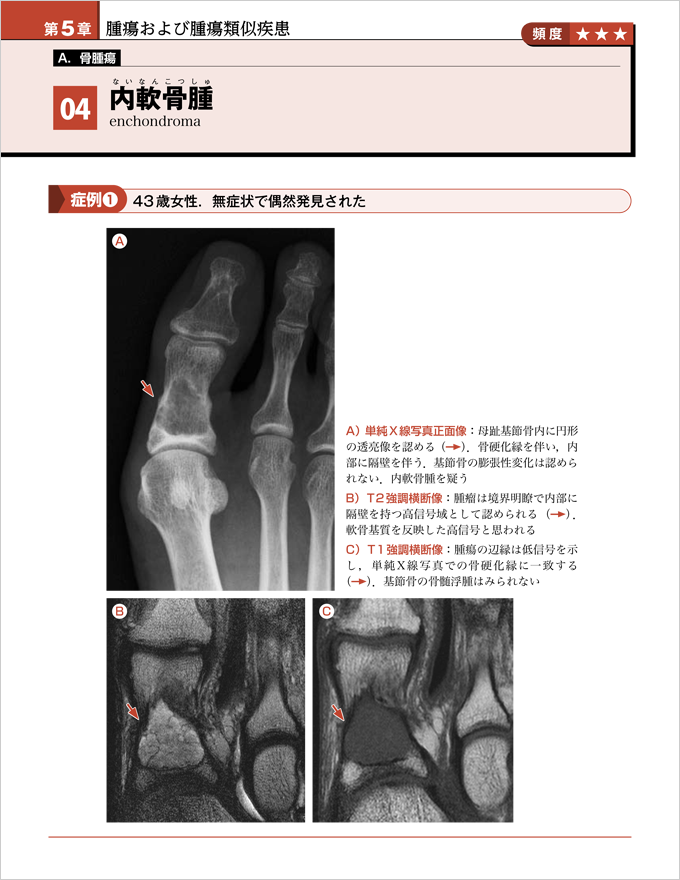

第5章 A. 骨腫瘍『04 内軟骨腫』より